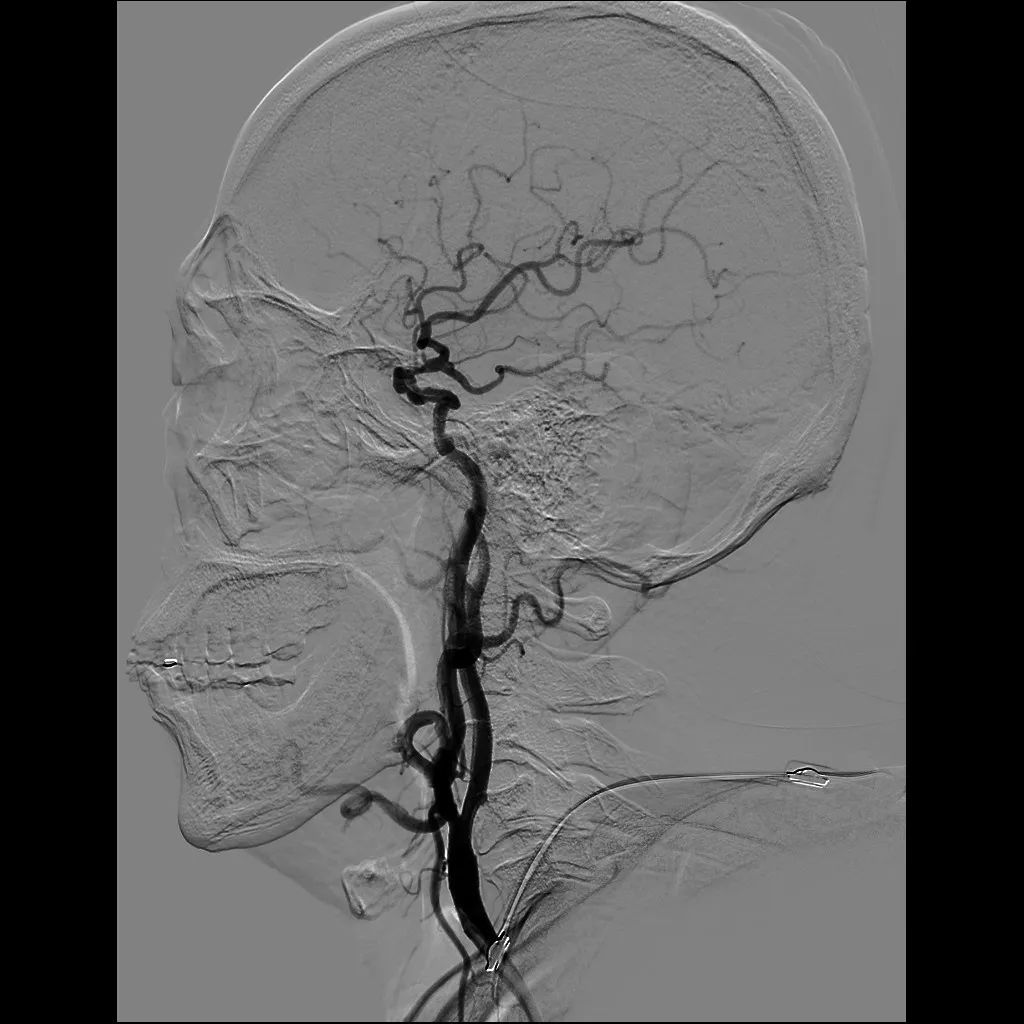

患者李某某,青年男性,因“右侧肢体活动不灵”入院,经头颈部CTA证实患者存在大脑中动脉狭窄,心电图示患者心脏供血不足,具备脑血管造影和心脏血管造影的指征。王司清主任查房后,制订了详细的治疗方案,并请心内科会诊协助治疗心脏供血不足。

经过会诊讨论,神经内一科与心内科医师决定同时进行脑血管造影和冠状动脉血管造影,但由于两处造影所需手术器械不同,药物应用不同,为避免长时间手术,两科详细制定了手术方案,合理安排手术顺序,先进行脑血管造影术,后进行冠转动脉造影术,经过密切配合,仅用时40分钟就完成了造影。造影证实患者存在大脑中动脉狭窄和冠状动脉狭窄,但好在患者狭窄程度未达到支架植入的指征,继续抗血小板聚集、调脂稳斑等药物治疗,患者病情逐渐稳定并好转出院。